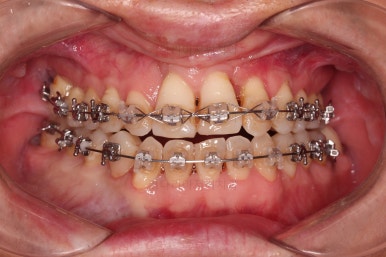

6. 마무리와 치료종료

부산구순구개열교정 종료 시의 입안의 모습입니다.

위아랫니 정렬이 잘 되었고, 치아 갯수가 위아래가 다르지만 교합도 나쁘지 않게 마무리가 되었습니다.

대문니 2개가 예후가 안좋긴 하나 양옆 치아들과 유지철사로 부착해 두어 최대한 오래 조심히 써보기로 했습니다.